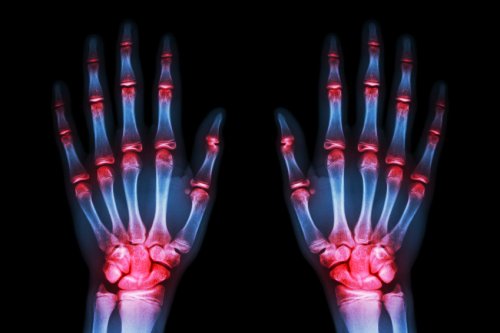

Osteoartritis treft 52% van de vrouwen tegenover 29% van de mannen. De eerste symptomen komen over het algemeen te voorschijn tussen 54e en 60e levensjaar en volgen dit patroon:

- Osteoartritis komt het meeste voor in de handen (70%)

Wanneer we naar de dokter gaan, op zoek naar hulp, is dit omdat we de pijn niet langer kunnen verdragen. De pijn in de handen is vreselijk. Ze tintelen ‘s nachts en worden langzaamaan misvormd.